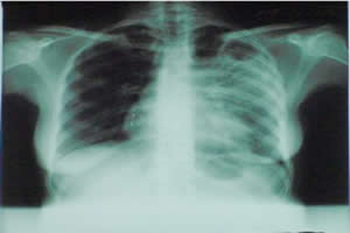

tuberculose

A FDA, agência que regula os alimentos e medicamentos nos Estados Unidos, aprovou um novo medicamento para combater a tuberculose pulmonar multirresistente.

A tuberculose, causada pela bactéria Mycobacterium tuberculosis, é uma das doenças mais mortíferas do mundo.